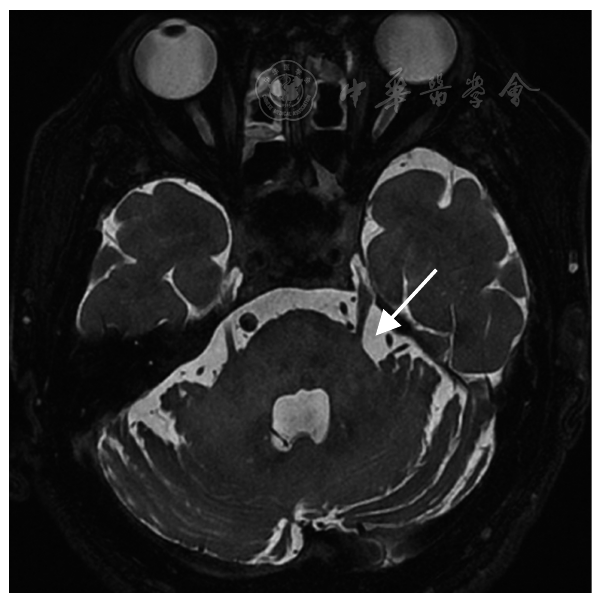

图3 CT引导下经皮下颌神经射频热凝术,双针同时进入卵圆孔内(箭头所示)

Fig.3 CT-guided percutaneous mandibular nerve radiofrequency thermocoagulation with dual needles simultaneously inserted into the foramen ovale (as indicated by the arrow)